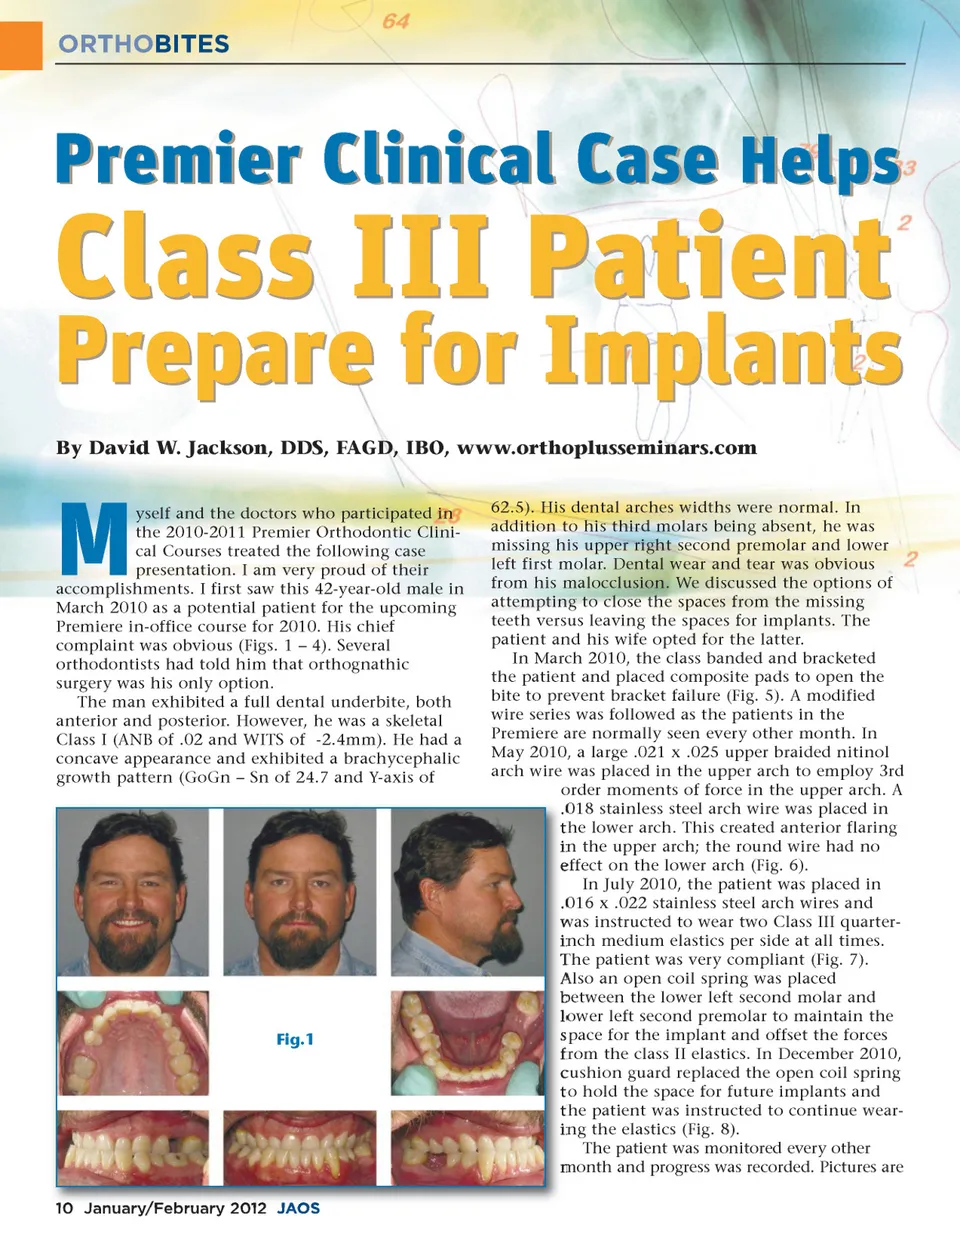

ORTHOBITES Premier Clinical Case Helps Class III Patient By David W. Jackson, DDS, FAGD, IBO, www.orthoplusseminars.com Prepare for Implants M yself and the doctors who participated in the 2010-2011 Premier Orthodontic Clini-cal Courses treated the following case presentation. I am very proud of their accomplishments. I first saw this 42-year-old male in March 2010 as a potential patient for the upcoming Premiere in-office course for 2010. His chief complaint was obvious (Figs. 1 – 4). Several orthodontists had told him that orthognathic surgery was his only option. The man exhibited a full dental underbite, both anterior and posterior. However, he was a skeletal Class I (ANB of .02 and WITS of -2.4mm). He had a concave appearance and exhibited a brachycephalic growth pattern (GoGn – Sn of 24.7 and Y-axis of Fig.1 62.5). His dental arches widths were normal. In addition to his third molars being absent, he was missing his upper right second premolar and lower left first molar. Dental wear and tear was obvious from his malocclusion. We discussed the options of attempting to close the spaces from the missing teeth versus leaving the spaces for implants. The patient and his wife opted for the latter. In March 2010, the class banded and bracketed the patient and placed composite pads to open the bite to prevent bracket failure (Fig. 5). A modified wire series was followed as the patients in the Premiere are normally seen every other month. In May 2010, a large .021 x .025 upper braided nitinol arch wire was placed in the upper arch to employ 3rd order moments of force in the upper arch. A .018 stainless steel arch wire was placed in the lower arch. This created anterior flaring in the upper arch; the round wire had no effect on the lower arch (Fig. 6). In July 2010, the patient was placed in .016 x .022 stainless steel arch wires and was instructed to wear two Class III quarter-inch medium elastics per side at all times. The patient was very compliant (Fig. 7). Also an open coil spring was placed between the lower left second molar and lower left second premolar to maintain the space for the implant and offset the forces from the class II elastics. In December 2010, cushion guard replaced the open coil spring to hold the space for future implants and the patient was instructed to continue wear-ing the elastics (Fig. 8). The patient was monitored every other month and progress was recorded. Pictures are 10 January/February 2012 JAOS